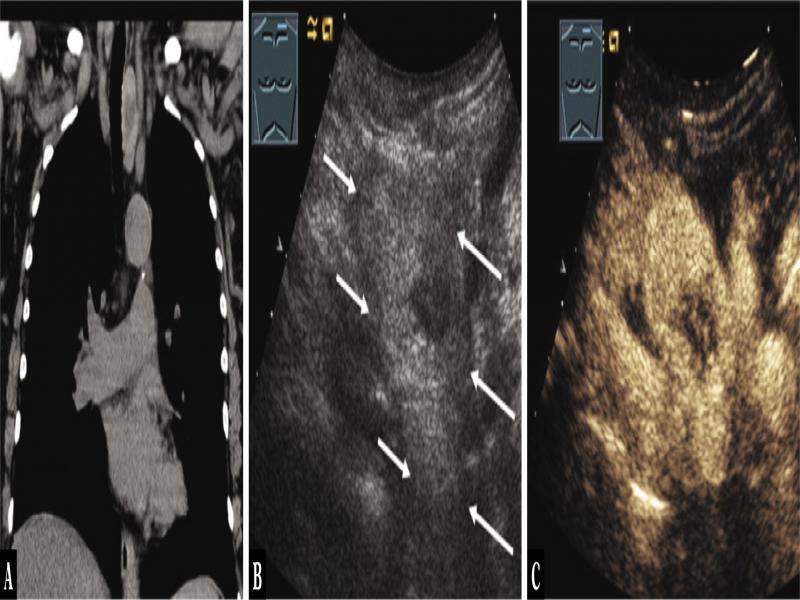

Fig. 3.

A 75-year-old female patient with mediastinal tumor in the anterior mediastinum as an incidental finding on computed tomography (A). Thoracic ultrasound indicated a hypoechoic inhomogeneous tumor (arrows) (B), which showed marked enhancement on contrast-enhanced ultrasound (C). A mediastinal thyroid gland was diagnosed by scintigraphy